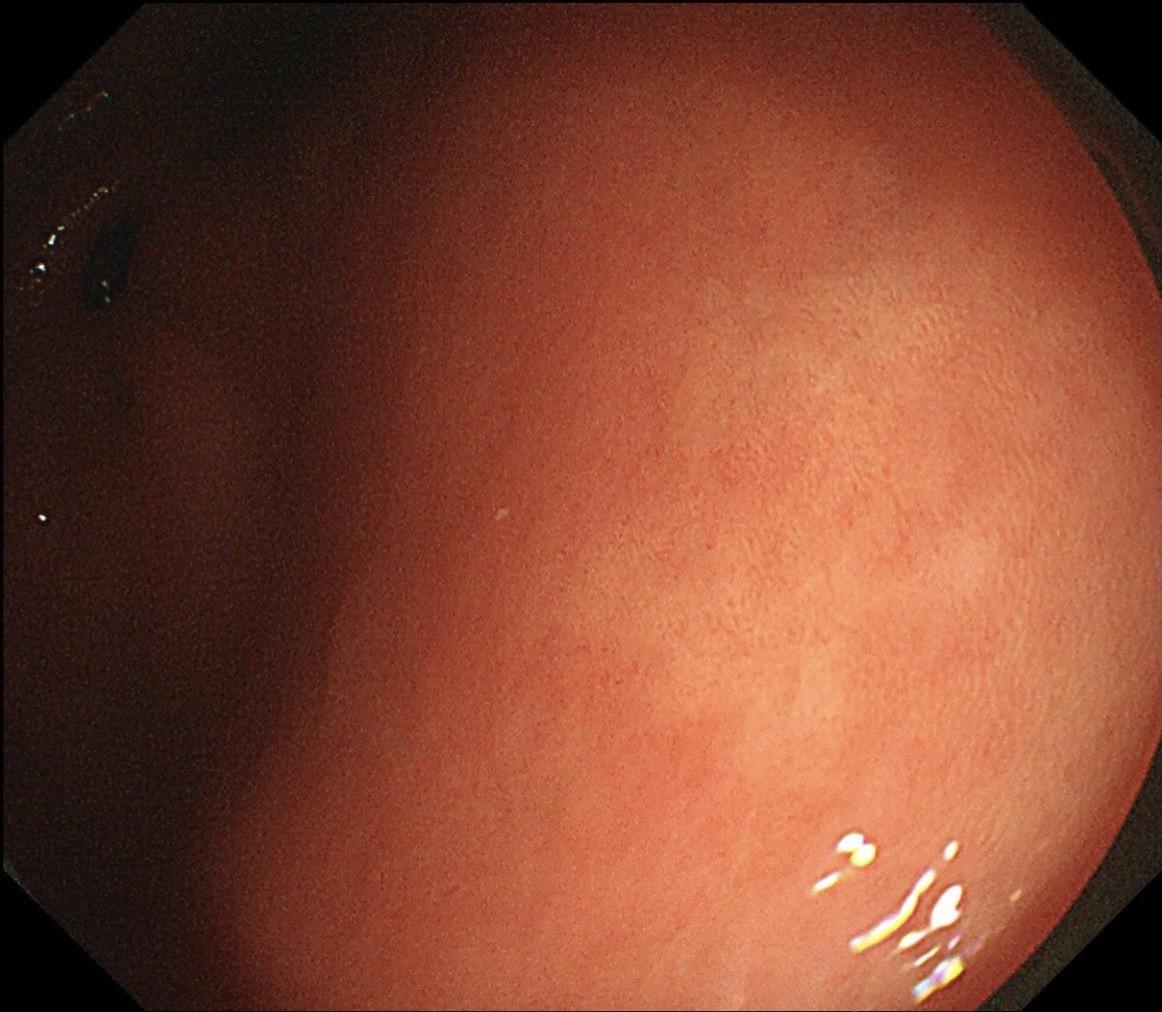

男,40岁,胃双发褪色调病变。慢性胃炎复查,3年前胃镜未见异常,Hp阳性背景,萎缩不明显,胃体下部大弯见一褪色调病变,浅凹陷,5mm左右,换用放大内镜观察,表面结构缺失,血管异型明显,未分化可能性大……胃窦后壁见一白斑,无高度差,NBI浅茶色,放大草草看了下,似有边界,IP增宽,活检待病理……小哥哥胖得几乎没脖子,腹式呼吸太明显~😖